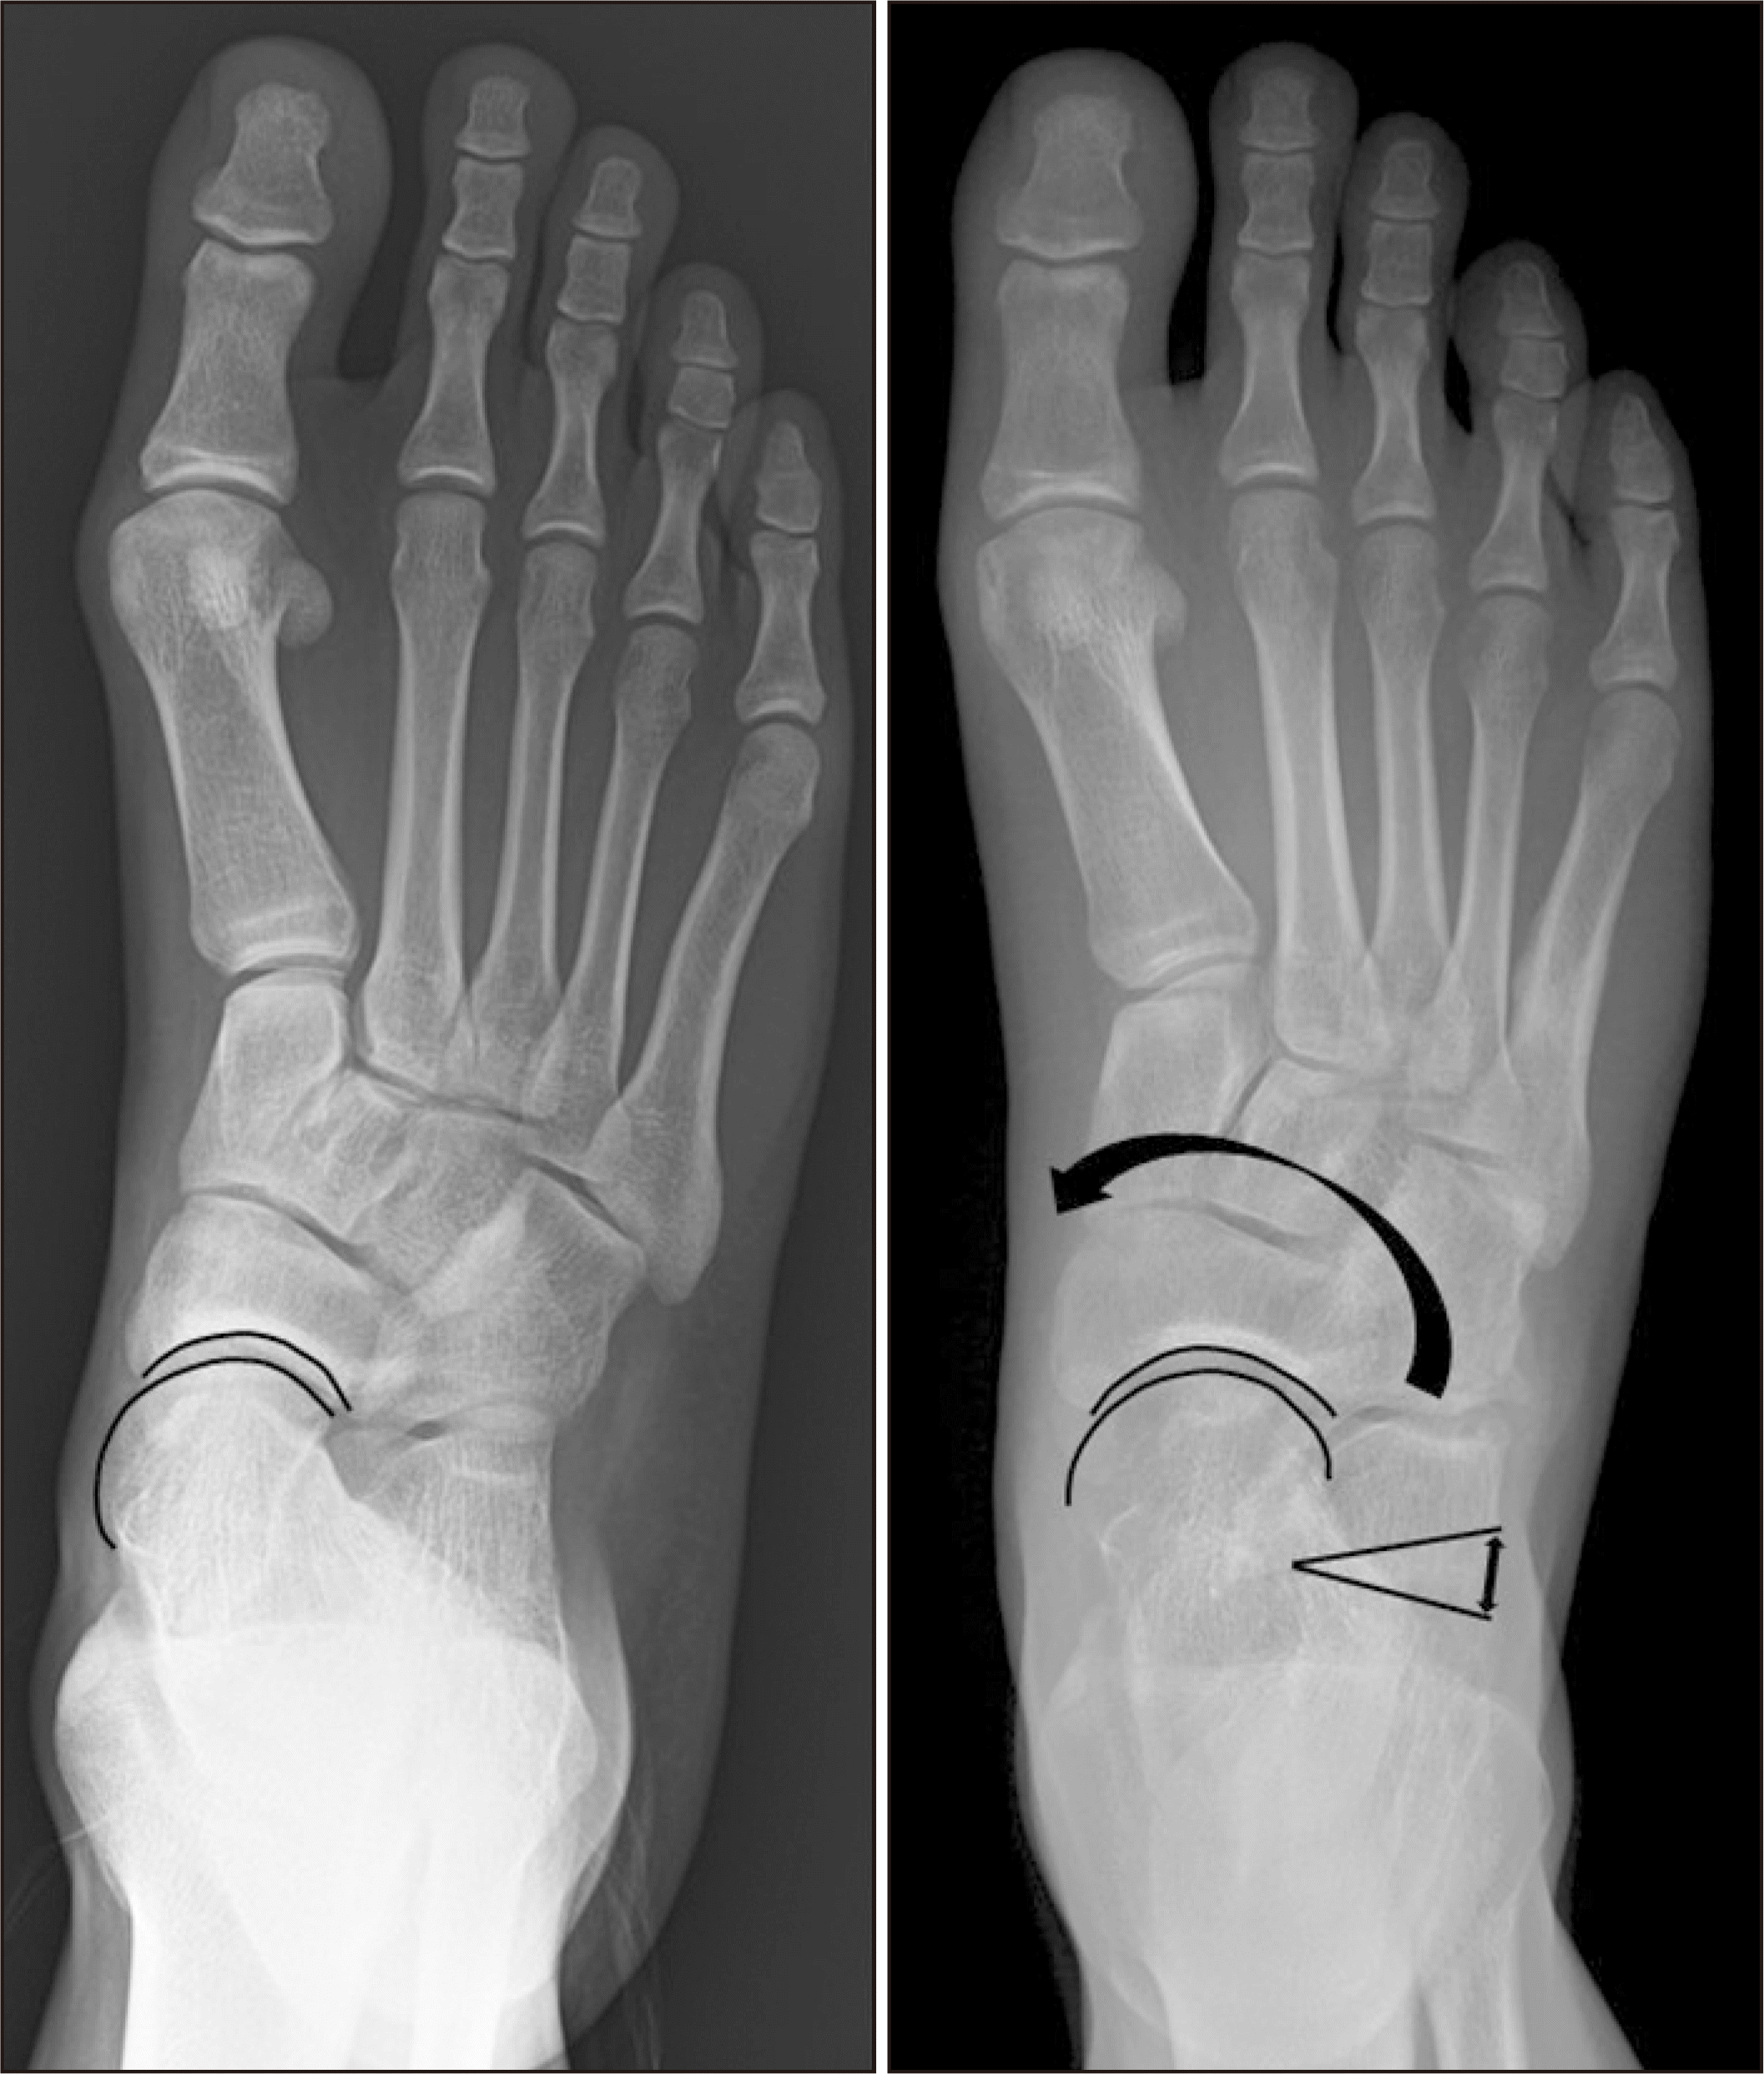

체중부하 방사선 촬영은 편평족의 진단에 있어 가장 표준이 되는 검사로, 체중부하 족부 전후면, 족부 측면, 족관절의 전후면 혹은 모티스 영상(mortise view) 및 후족부 정렬 촬영(hindfoot alignment view)8) 등이 진단을 위해 권고된다.9) 족부 전후면 사진에서는 전족부 혹은 중족부의 외전 정도를 평가할 수 있으며 거주상 관절 피복각(talonavicular coverage angle), 거주상 관절 이탈률(talonavicular uncoverage percent) 등 이를 반영하는 매우 다양한 지표를 측정할 수 있다(Fig. 1). 족부 측면 사진에서는 내측 세로궁의 소실 정도를 평가할 수 있는데, 흔히 쓰이는 지표로는 Meary angle이라 불리는 외측 거골-제 1중족골 각도를 측정할 수 있다(Fig. 2). 또한 족부의 내측주(medial column) 관절들의 족저부 벌어짐(plantar gapping) 정도를 확인하여 내측주 불안정성 정도를 평가할 수 있으며 족근동에서 거골과 종골의 직접적인 충돌 혹은 족근동 주변 골의 경화소견이나 낭종성 병변 등을 통해 족근동 충돌을 간접적으로 확인할 수 있다(Fig. 3). 족관절의 전후방 혹은 모티스 사진에서는 거골의 외반경사(valgus talar tilt)의 유무를 통해 족관절의 불안정성을 평가할 수 있으며 변형이 많이 진행한 경우 비골하 충돌 또한 확인할 수 있다(Fig. 4). 마지막으로, 후족부 정렬 촬영을 통해서는 후족부 외반 변형의 정도를 평가할 수 있는데, 주로 후족부 정렬각(hindfoot alignment angle) 혹은 후족부 모멘트암(hindfoot moment arm)을 측정한다(Fig. 5).10)

새로운 분류체계는 변형의 종류와 위치에 따라 A~E로 나누고, 각 변형의 유연성 유무에 따라 1기 유연성 변형과 2기 강직성 변형으로 분류하였다(Table 2).6) 이러한 변형은 진찰 소견과 체중부하 단순 방사선 촬영을 통해 평가하도록 하였고, 체중부하 전산화 단층촬영의 경우 아직 전세계적으로 사용되고 있지는 않기 때문에 판단기준에서 제외되었다. A형 변형은 후족부 외반 변형으로 후족부가 신체의 정중선으로부터 외측으로 전위된 변형을 뜻한다. 임상적으로 진찰 시 후족부 외반이 관찰되거나, 후족부 정렬 영상에서 후족부 정렬각 혹은 후족부 모멘트암의 증가 등으로 판단할 수 있다(Fig. 5). B형 변형은 전족부 혹은 중족부의 외전 변형으로 전족부나 중족부가 후족부를 기준으로 외측으로 전위된 변형이다. 체중부하 족부 전후면 사진상 거골두에 대한 주상골의 피복(coverage) 정도가 감소하고, 거주상 관절 피복각이 증가한다(Fig. 1). 또한 이 변형에 의해 족근동 충돌이 발생할 수 있으며, 족근동 주변의 압통 및 통증이 발생할 수 있다. 체중부하 족부 측면사진상 족근동에서 거골과 종골의 직접적인 충돌 소견이 보이거나, 족근동 주변의 거골과 종골의 골경화 혹은 골낭종 등을 통해 간접적으로 확인할 수 있다(Fig. 3). C형 변형은 전족부의 내반 변형 혹은 내측주 불안정성으로 임상적으로 후족부를 중립 위치에 고정한 뒤 관찰하였을 때 전족부가 내반을 보이는 변형이다(Fig. 8). 일부에서는 이를 회외 변형으로 불러야 한다는 의견도 있으나 현재 혼용해서 쓰이고 있다.11,20) 내측주 불안정성은 체중부하 족부 측면사진상 거주상 관절, 주상설상 관절(naviculocuneiform joint) 및 족근중족 관절(tarsometatarsal joint)이 배측 불안정증을 보이는 것으로, 영상검사상 족저부 벌어짐 유무 등을 통해 내측주 불안정성의 유무 및 위치를 확인할 수 있다(Fig. 3). D형 변형은 거근관절의 탈구 혹은 아탈구 변형으로 거골이 종골을 기준으로 내회전, 족저굴곡되면서 종골은 거골을 기준으로 외회전, 외반, 외측 전위가 발생하면서 거골하 관절의 아탈구가 발생하고, 심한 경우 비골하 충돌을 일으키게 된다(Fig. 4). E형 변형은 발목관절의 외반 변형이 발생한 경우이며, 족관절의 전후방 혹은 모티스 사진에서 거골의 외반경사로 확인할 수 있다(Fig. 4). 이 분류의 적용은 한 환자에 대해 A 부터 E까지의 변형 유무를 확인하고, 각각의 변형이 유연성 변형인지, 강직성 변형인지에 따라 1기와 2기를 나누는 방식으로 적용한다.